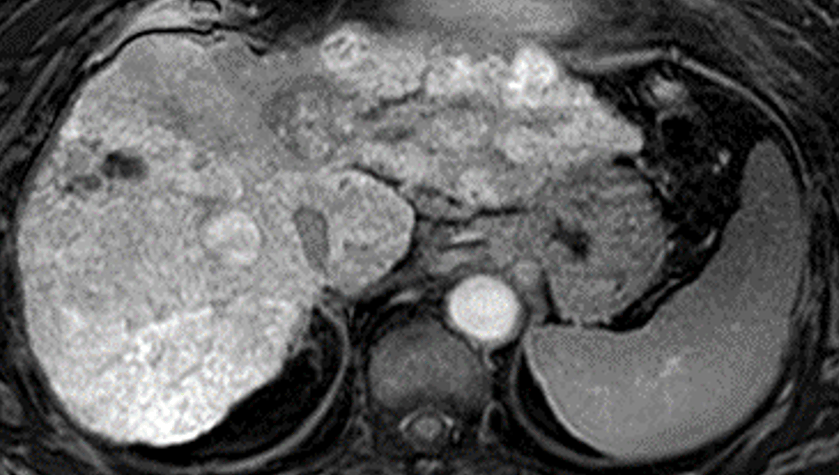

EOB-MRIは、肝がん診療には欠かせない、日常的に広く行われている検査の一つです。肝がん患者において、免疫チェックポイント阻害剤療法の直前に撮影されたEOB-MRIの画像とその後の病状の経過を調べたところ、画像中に背景の肝臓と比べて同等または少し白く映ったしこり(結節)は、免疫チェックポイント阻害剤療法の効果が少なく、増大する速度が速いことが示されました。

本研究は、Wnt/β-カテニンシグナル※3 の活性化状態が、EOB-MRIの肝細胞相※4 において、背景の肝臓より信号強度が高いか等しい結節(等~高信号結節)として現れるという仮説に基づき、切除不能肝がんに対する免疫チェックポイント阻害剤の治療抵抗性を予測することを目的として行われました。免疫チェックポイント阻害剤単独療法の直前にEOB-MRIを撮影していた18症例68結節を対象としており、その内訳は、背景の肝臓より信号強度が高いか等しい結節(等~高信号結節)が23個、背景の肝臓より信号強度が低い結節(低信号結節)が45個でした。

これらの症例について、EOB-MRIの肝細胞相を調べたところ、等~高信号結節を有する患者では、治療効果があった患者の割合(ORR)は12.5%、病勢コントロール率(DCR)は37.5%でした。一方、低信号結節のみを有する患者では、治療効果があった患者の割合は30.0%、病勢コントロール率(DCR)は70.0%でした。また、無増悪生存期間中央値※5(PFS中央値)は、等~高信号結節の患者で2.7カ月、低信号結節の患者で5.8カ月。各結節が20%以上増大するまでの時間の中央値は、等~高信号結節では1.97カ月、低信号結節では未達(半数以上の結節で増大を示さない結果)でした。

これによって、EOB-MRIの肝細胞相で等~高信号を示した結節は、低信号を示した肝がんと比較して、免疫チェックポイント阻害剤単独療法の効果が有意に劣ることが明らかになりました。また、等~高信号結節は免疫チェックポイント阻害剤の治療中により早く増大し、腫瘍が再発あるいは進行するまでの期間が有意に短くなることも示されました。これらの結果は当初の仮説を裏付けるものであり、EOB-MRIの肝細胞相において、等~高信号の結節が免疫チェックポイント阻害剤単独療法の反応性低下を予測するバイオマーカーになり得るということを強く支持するものでした。

※3 Wnt/β-カテニンシグナル:Wnt/β-カテニンは、肝細胞がんや他のがんで検出される細胞増殖能が増強する遺伝子変異の一つ。遺伝子が活性化することで腫瘍を取り巻く環境では様々な情報伝達が起こるが、この遺伝子が活性化することにより、OATP1B3という輸送体が増えるため、EOB-MRIで用いられる造影剤が腫瘍内に取り込まれて高信号結節(白い結節)として認識できる。この遺伝子変異はがん細胞に対する免疫機能を低下させる役割も持っており、一般的に免疫チェックポイント阻害剤が効きにくいといわれている。

※4 肝細胞相:肝特異的造影剤「EOB/プリモビストR(ガドキセト酸ナトリウム)」を投与し、20~40分ほど経過してから撮像するT1強調画像。肝細胞がんでは、一般的にOATP1B3という輸送体の発現が低下するため、細胞内への造影剤の取り込みが低下し、低信号の結節として描出される。一方、OATP1B3の発現が増えると、細胞内へ造影剤の取り込みが亢進して、高信号の結節として描出される。